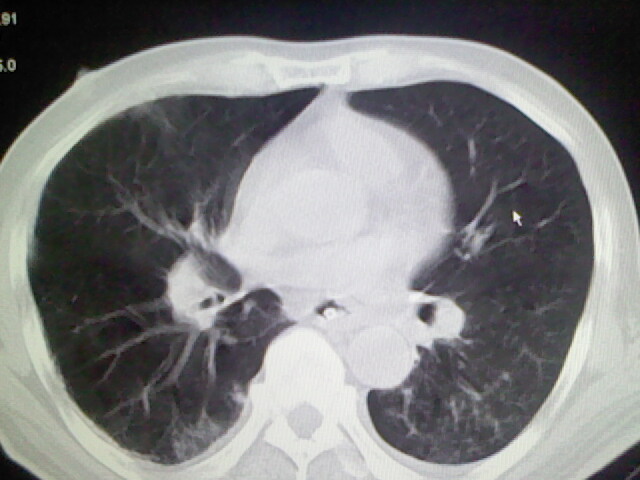

男,70岁,脑出血,长期卧床,左侧背部可触及肿块

右肺病灶考虑炎症性。

考虑右肺及左肺下叶炎症。

右肺及左肺下叶炎症。

考虑右肺及左肺下叶慢性炎症。

右侧肺部见片状密度增高影,边缘模糊。考虑炎症。另食管壁增厚。

右肺上叶前段病呈楔形,其尖端指向肺门,考虑肺动脉栓塞可能性大.